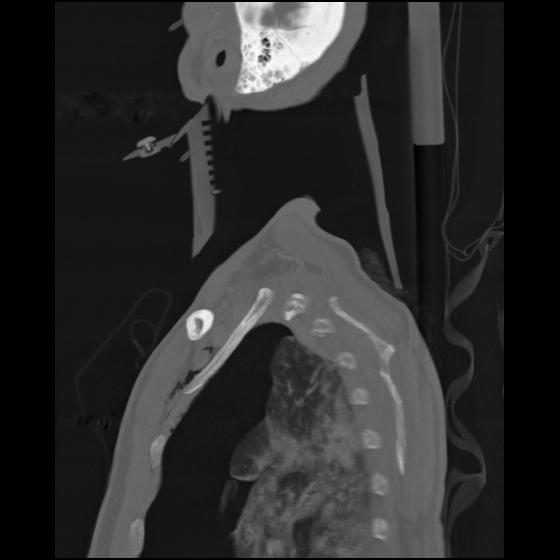

24 ANGIO,CE,Sag-MIP,5.000,ANGIO,Sag-MIP,